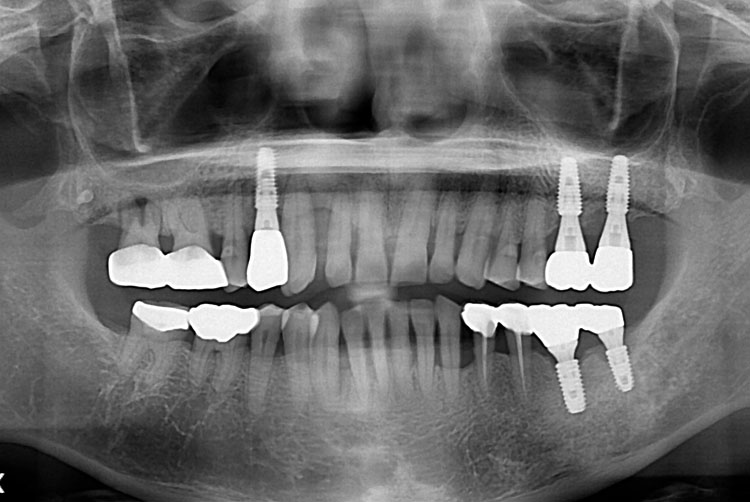

치료후 : 2018-09-11

세종치과는 많은 환자와 다양한 케이스를 바탕으로 항상 편안한 임플란트 수술을 제공하고자 노력하고,

오래동안 튼튼히 쓸 수 있는 임플란트 수술을 가장 큰 목표로 삼고 있습니다.